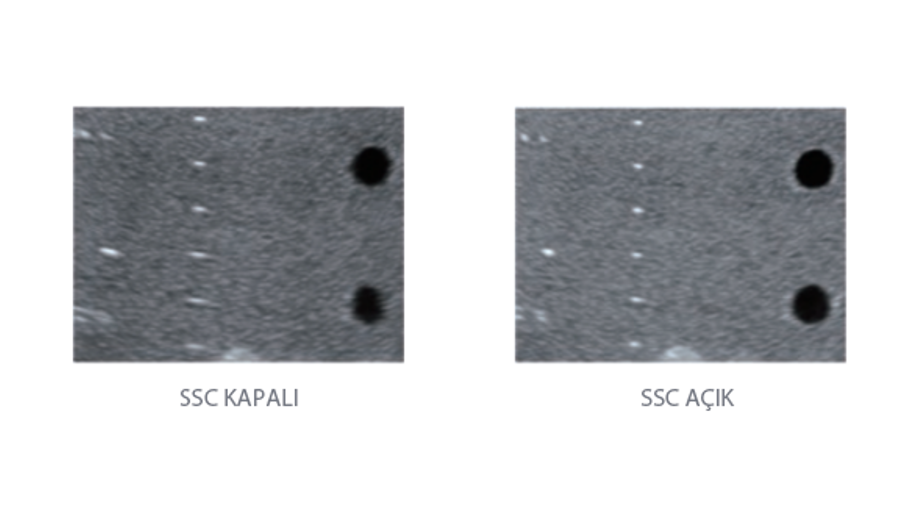

Mindray, ?irketin kuruldu?u gĂŒnden bu yana sĂŒrekli olarak tan?sal do?rulu?u iyile?tirmeye ?al??maktad?r. Devrim niteli?indeki ZONE Sonography? Teknolojisi ile desteklenen Resona 7ânin yeni ZST+ platformu, b?lge g?rĂŒntĂŒsĂŒ alma ve kanal veri i?leme ?zellikleri ile ultrason g?rĂŒntĂŒsĂŒ kalitesini daha ĂŒst bir dĂŒzeye ??kar?yor.